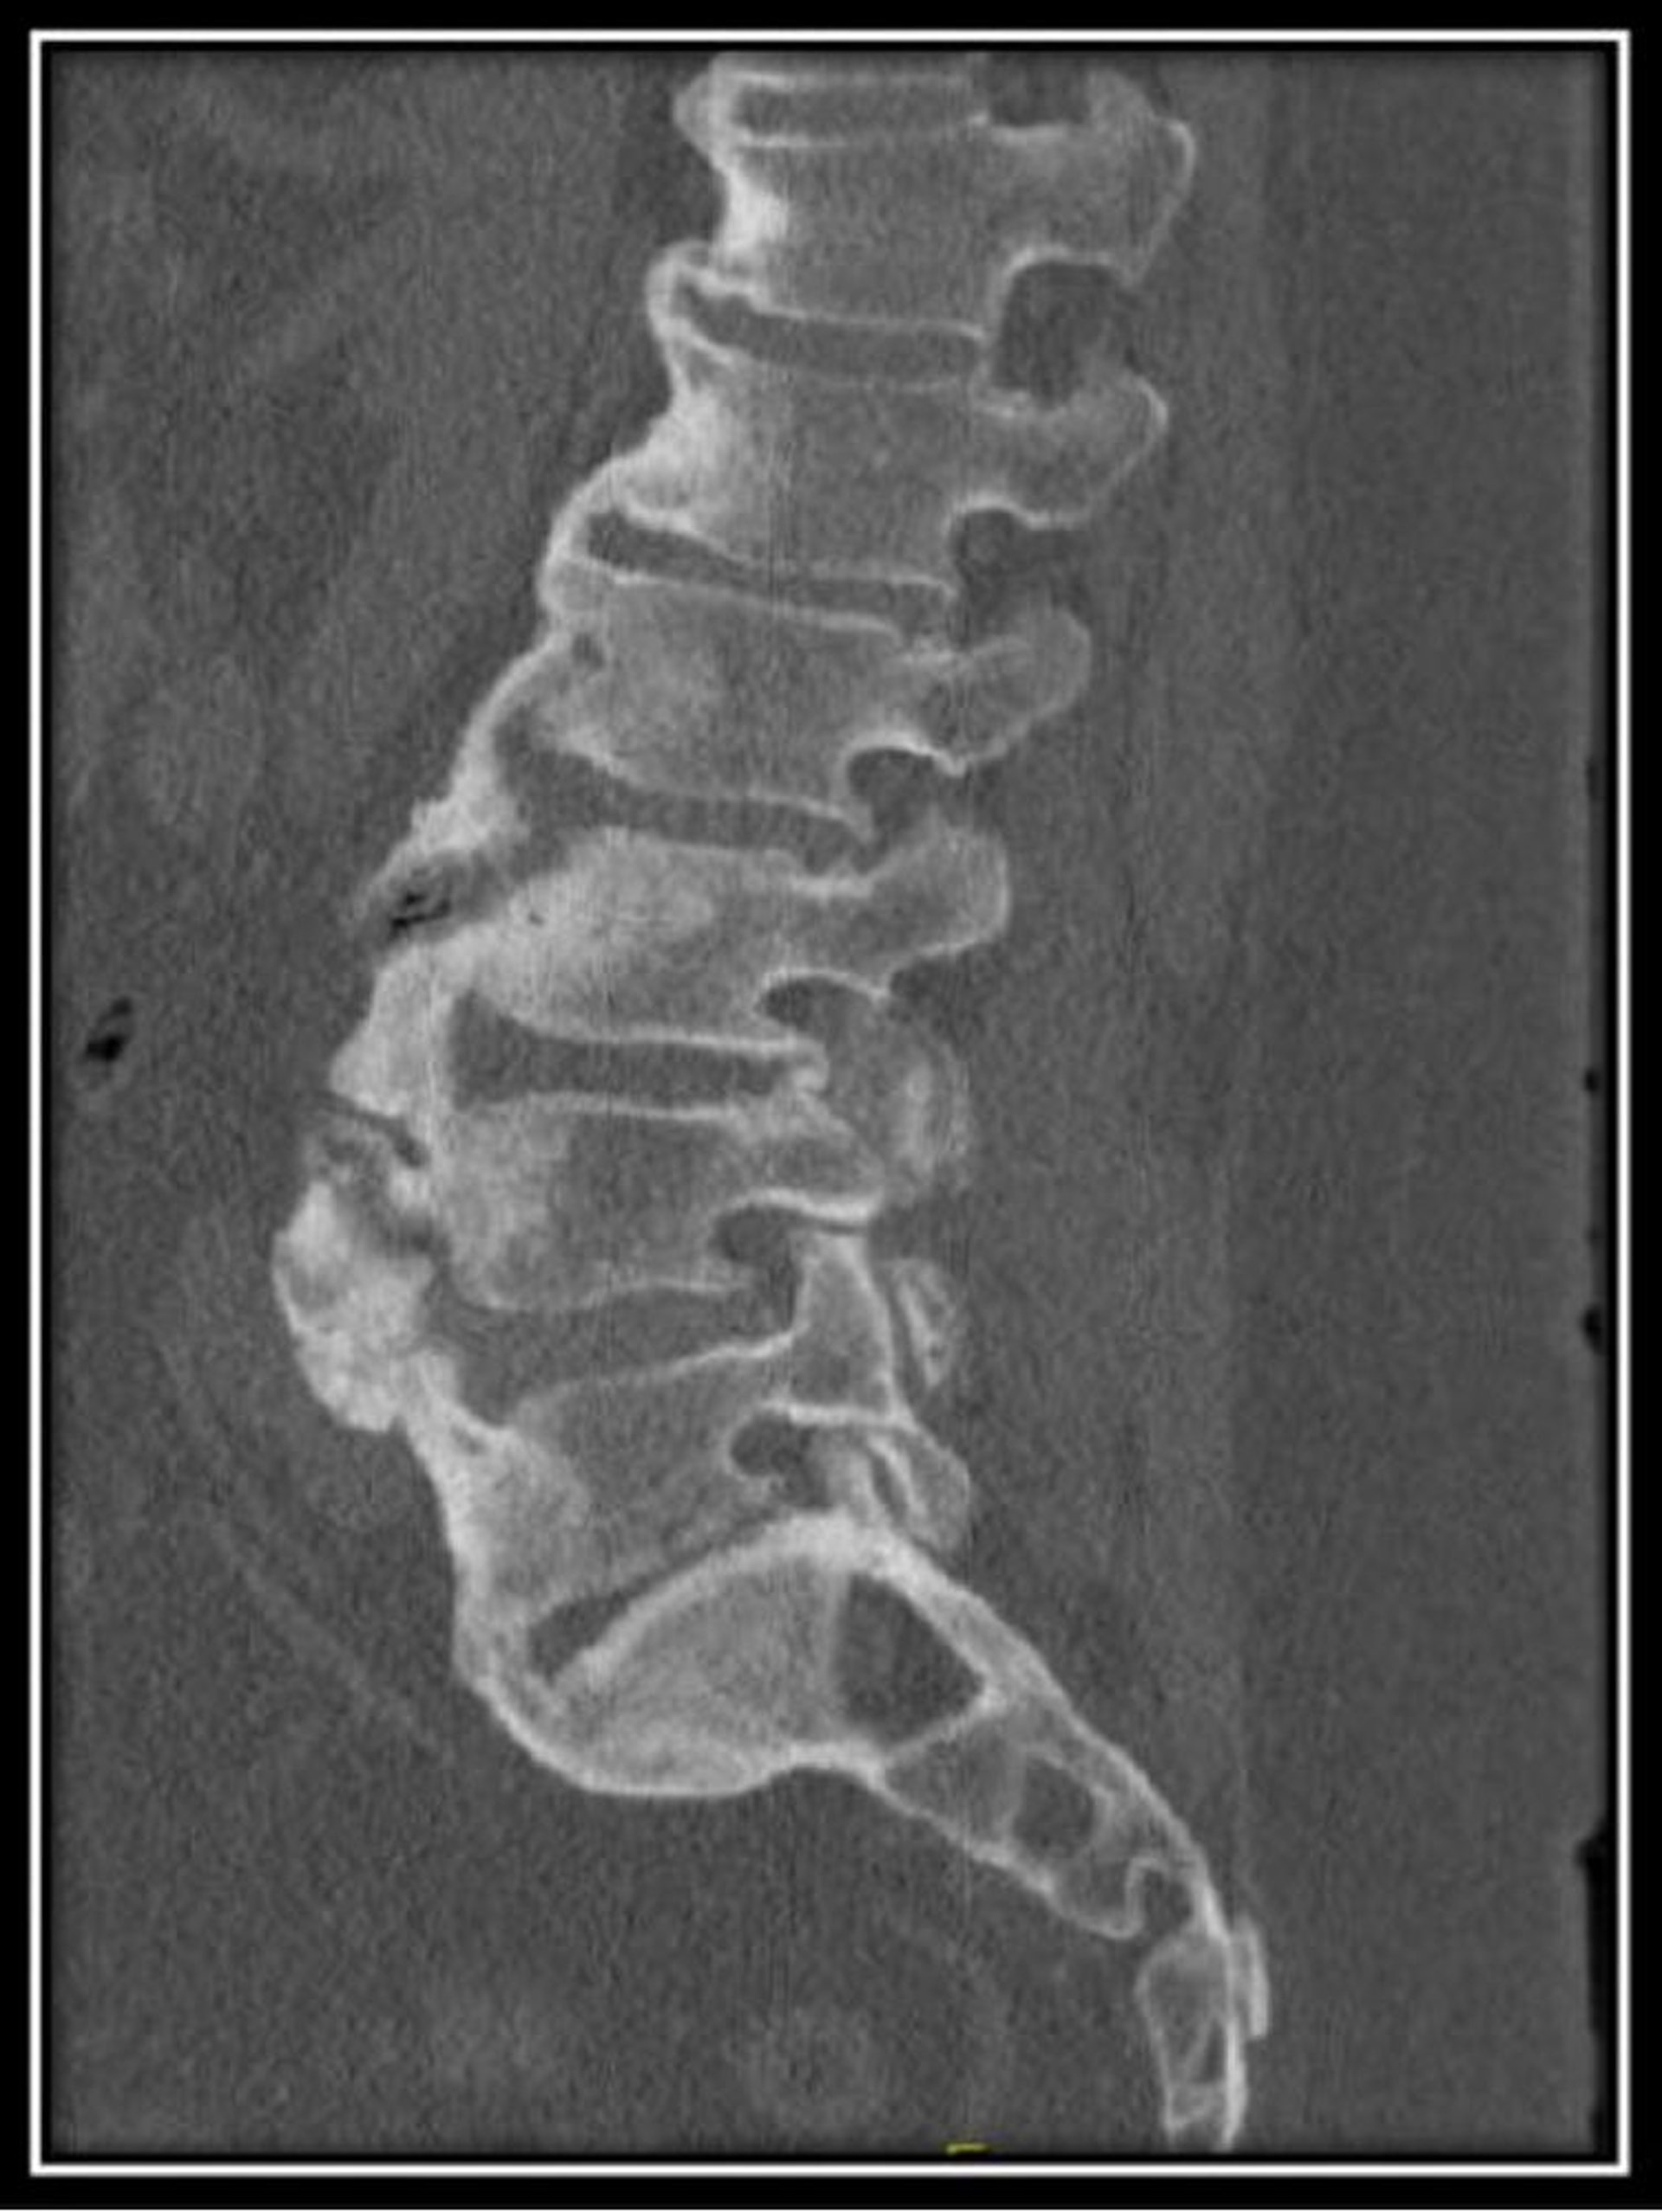

Iperostosi scheletrica idiopatica diffusa (TC)

Questa scansione TC della colonna lombare in un paziente con iperostosi scheletrica idiopatica diffusa mostra normali altezze del corpo vertebrale con osteofiti diffusi a flusso anteriore con spazi del disco mantenuti.

Image courtesy of Kinanah Yaseen, MD.